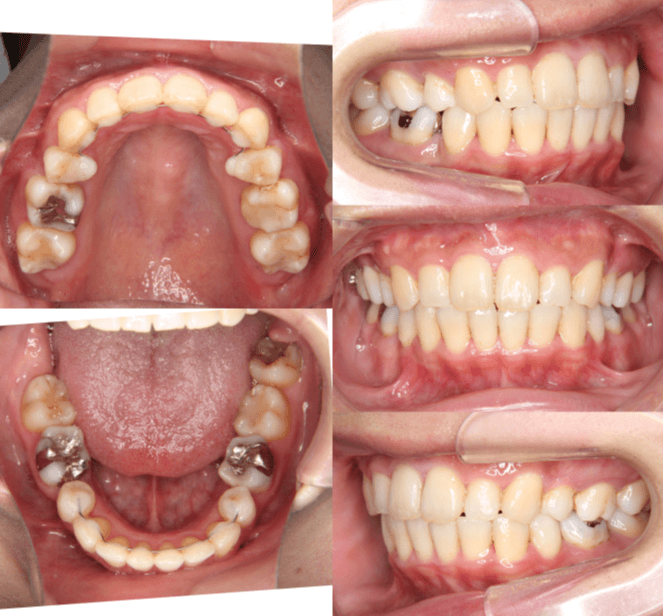

開咬と口元の突出感が気になる

| 年齢・性別 | 22歳の女性 |

|---|---|

| 主訴 | 上下顎前歯部に開咬と口元の突出感を気にされて来院された。咬み合わせや審美的な改善を希望されていました。 |

| 治療期間・回数 | 3年9ヶ月・32回 |

| 費用 | 930,000円 |